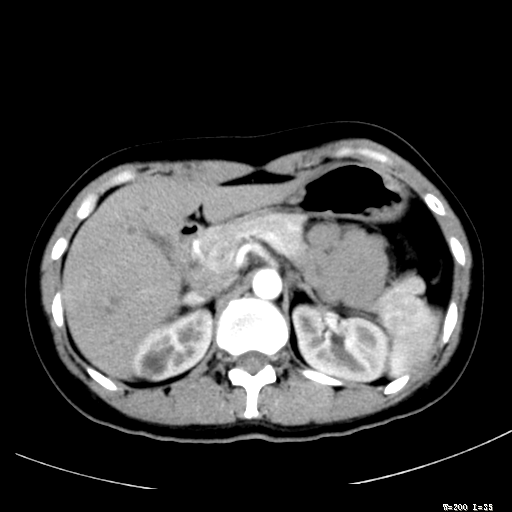

标题: CT25345:右肾占位。

女,30岁,右腰部胀痛3个月。

增强无明显强化,先考虑血管平滑肌脂肪瘤,建议作薄层扫描右mri检查,

感觉像囊肿.

囊肿!

考虑右肾近上极囊肿;建议必时行mri检查。